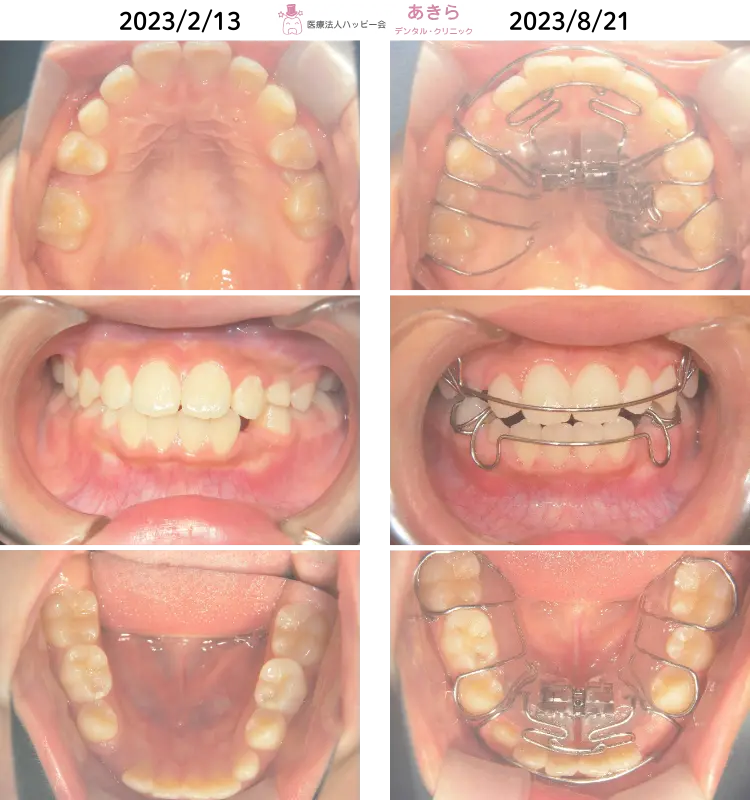

2023年2月13日 初診時 ⇒ 8月21日 上顎SHA修理時

- 矯正2期治療として2023年3月より「SHA=SH装置」SH療法スタート

- 永久歯の抜歯をしないで上顎左右5番を萌出させるべく治療計画を立案しました。

- 上下顎狭窄歯列の解除および右上6番の遠心移動を主に設計~スタートしました。

- 歯列が直立してくることにより早期接触がおこるため、随時必要枠での咬合調整が必要になります。

- 右上5番が萌出できたため、左上5番萌出を促すSHA(SH装置)修理設計を施しました。

- SHA修理 上下1回